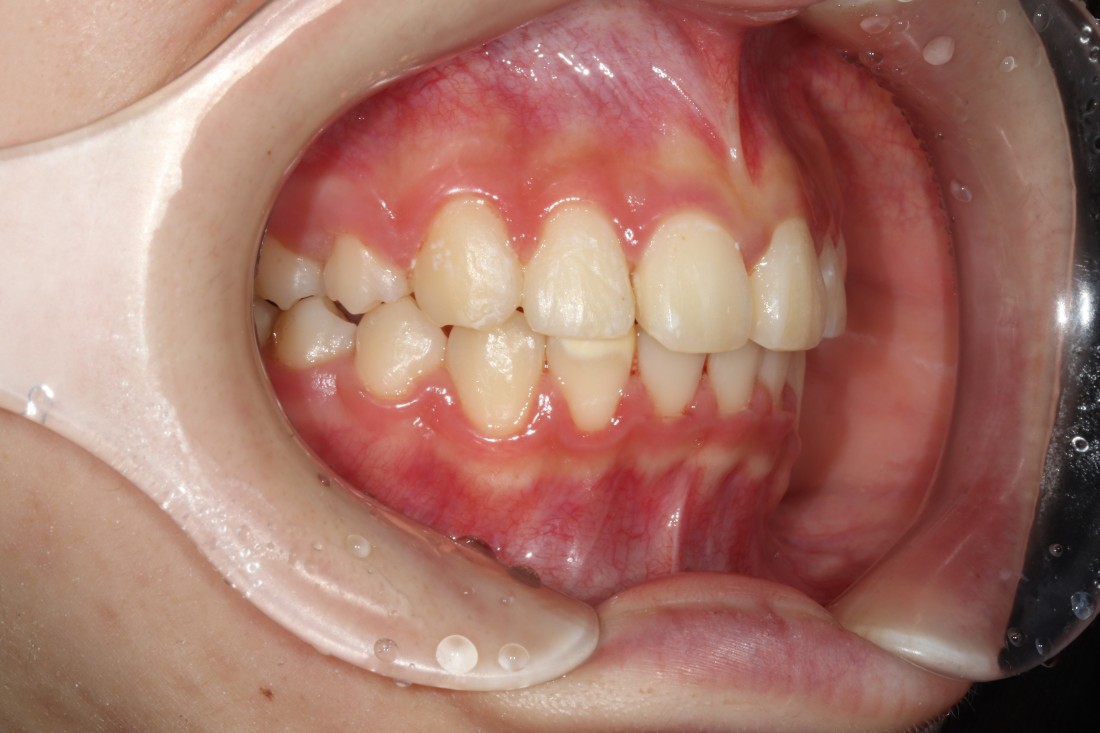

덧니는 과거에는 귀여운 이미지를 줘서

선호하기도 하였지만,

요즘은 고른 치열을 만들어서

세련된 외모를 완성하는 것이

필수 트렌드가 되고 있습니다.

광주 교정치과에서는

3차원 105항목 정밀검사를 통해

발치교정 / 비발치교정 을 포함하여

정확한 치료계획을 세우고 있습니다.